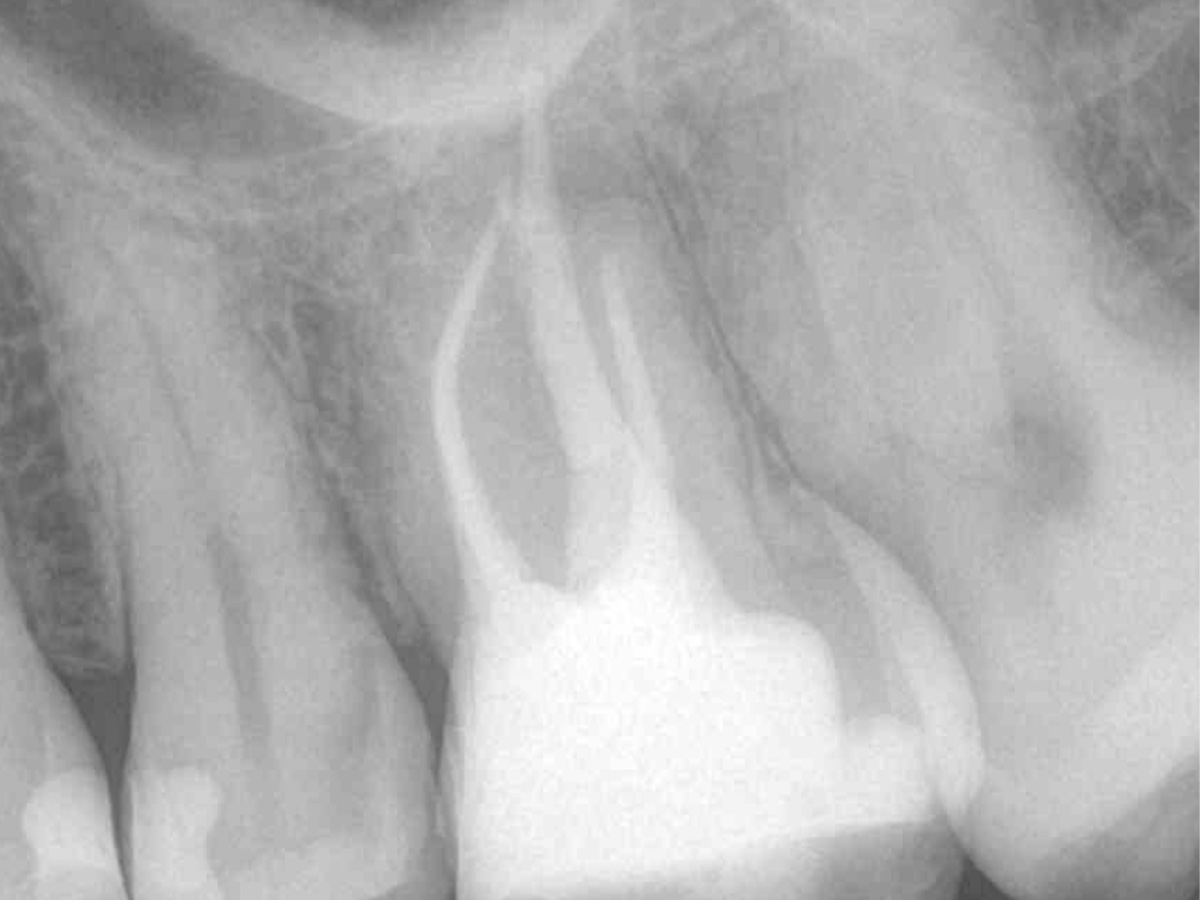

Die Arbeitslängen der Kanäle wurden mittels elektrometrischer Messung bestimmt und die Kanäle aufbereitet. Alle Kanäle außer dem palatinalen wurden bakteriendicht mit einer Sealer-basierten Wurzelfülltechnik (Guttapercha und TotalFill® BC Sealer) verschlossen.

Für den ovalen Querschnitt der palatinalen Wurzel wurde eine warm-vertikale Technik angewendet. Dazu wurde der Guttapercha Hauptstift mit dem B&L Alpha und einem Hitzeplugger (55/.08) in der Tiefe abgetrennt und kondensiert.

Mit dem B&L Beta wurde der restliche Kanal nach der Backfill-Technik schrittweise mit erwärmter Guttapercha aufgefüllt. Die abschließenden Röntgenaufnahmen zeigen das Ergebnis, das mit den kabellosen Systemen präzise und effizient umgesetzt werden konnte.

Abbildung 7

Wurzelfüllung 26 orthoadial